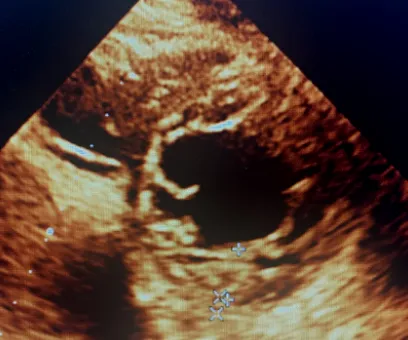

① 左室 ≥1 个节段室壁厚度 ≥15mm (图 3 ,图 4 ),有家族史者,厚度 ≥13mm (注意测量选择舒张末期,短轴切面测量心肌厚度**;

图 3 心尖四腔心切面可探及左室壁明显增厚,*厚处约 21mm

图 4 大动脉短轴切面显示左室壁增厚,*厚处约 21mm